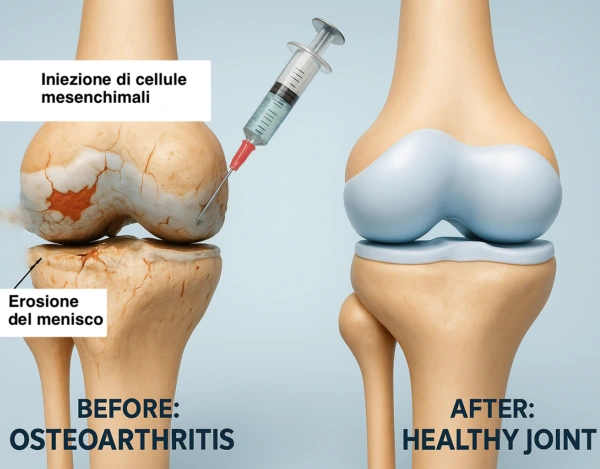

In un’osteotomia di ginocchio, la tibia e/o il femore, vengono tagliati e riallineati per redistribuire correttamente la forze all’interno del ginocchio. Al termine, i segmenti tagliati vengono ricongiunti usando dei mezzi di sintesi (placca e viti in titanio).

Se necessario, il difetto osseo creato può essere colmato con innesto di osso allograft (da donatore) o sintetico. Si ricorre all’osteotomia come intervento di salvataggio in alternativa o in attesa di un intervento di protesi di ginocchio, in un quadro di artrosi di ginocchio con presenza di ginocchio “varo” o “valgo”.

Attraverso l’osteotomia, il chirurgo corregge l’allineamento dell’arto inferiore, spostando l’asse di carico dal comparto danneggiato al centro dell’articolazione. In questo modo si ottiene una riduzione significativa del dolore e un miglioramento della funzionalità del ginocchio.

Preservazione dell’articolazione naturale, ritardando o evitando la necessità di una protesi.

Prevenzione della progressione artrosica nei soggetti giovani con deformità dell’asse.